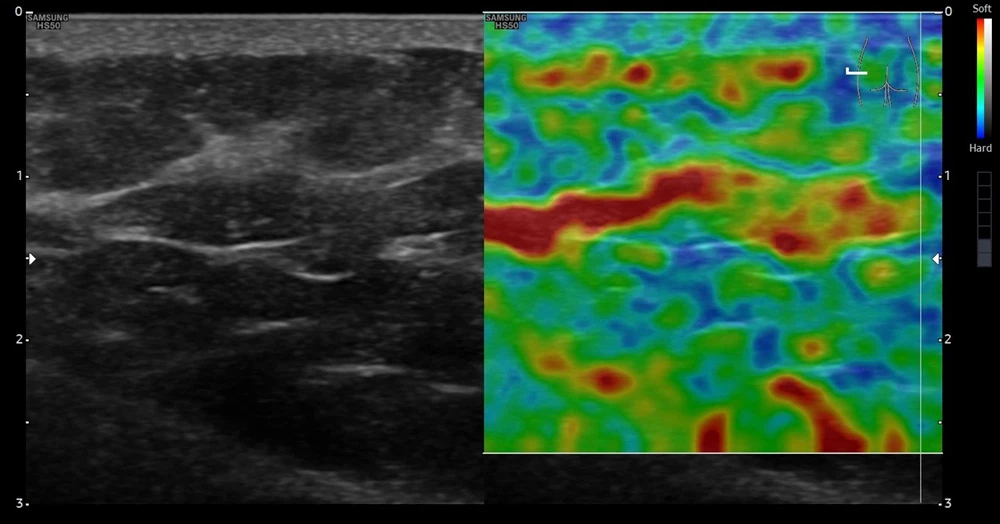

Эластосканы пациента до начала лечения. Правая сторона

При выполнении ультразвукового исследования кожи и подкожно-жировой клетчатки на аппарате экспертного класса линейным датчиком у пациента с целлюлитом в глютеофеморальной зоне до проведения терапии SKINOVA PRO Body при оценке качественной соноэластографии визуализировались участки с более низкой эластичностью (на снимках включения более мягких участков, окрашенных на эластоскане в оранжевые, красные цвета).

После курса лечения у пациента в тех же исследуемых участках при поверхностном сканировании в тех же точках наблюдалась значительно более высокая жесткость ткани (на снимках окрашены в синий и зеленый цвета).

Отмечается увеличение прочности на границе кожи и подкожной клетчатки.